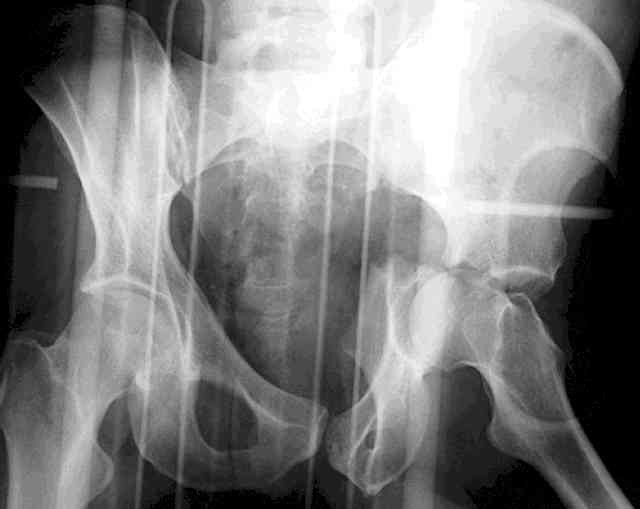

I'll include a few images of a similar injury in a similarly large male patient. This patient "showed up" in our ER c/o hip pain 2 months after being treated in the lateral position, without a quality reduction, without an anterior column transverse supporting implant, with an unbalanced plate applied too medially, with insufficient caudal segment fixation...it took over 8 hours and a 3+ l blood loss to debride the callus from front then

back, excise the HO, release his sciatic nerve, reduce the head-transverse-wall, and fix it...and now it's a staging procedure.